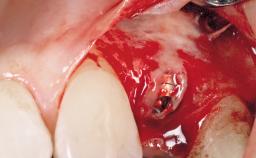

A 30-year-old female patient had lost tooth 21 and was referred to our clinic for consultation and treatment. Due to advanced apical infection, tooth 21 had been extracted two months earlier at another clinic and an acrylic-resin tooth had been bonded to the adjacent teeth. The patient desired implant treatment to avoid any damage to the adjacent natural teeth. While the patient had no history of any systemic disorder, she was a heavy smoker and exhibited medium to advanced periodontitis in the entire jaw. After the initial treatment to achieve a pocket probing depth of less than 4 mm and no bleeding on probing, a decrease in the height of the papillae mesial and distal to the extraction site and overall gingival recession were observed.

Type of Implants One-Piece|Reduced-Diameter

Placement Protocol Early or late implant placement